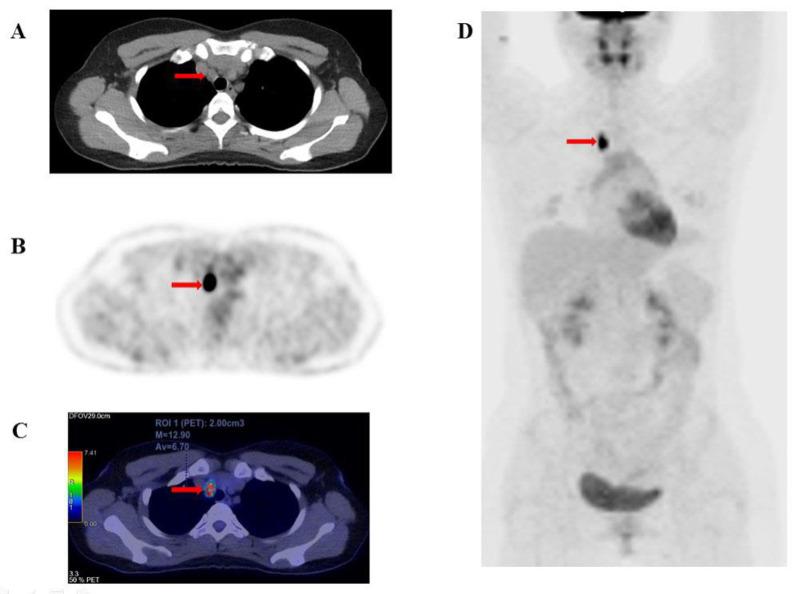

This study investigates the relationship between quantitative F-FDG PET/CT metabolic parameters and overall survival (OS) in patients with radioiodine-refractory differentiated thyroid cancer (RAI-R DTC).

We conducted a prospective analysis of 127 patients with RAI-R DTC. Quantitative metabolic parameters including SUV, SUV, SUV, total metabolic tumor volume (MTV), and total lesion glycolysis (TLG) were assessed in F-FDG -avid recurrent or metastatic lesions via F-FDG PET/CT imaging. Patients were monitored for disease progression and mortality for at least one-year post PET/CT imaging. Receiver operating characteristic (ROC) curves were used to establish cut-off values for predicting 5-year mortality, while the Kaplan-Meier method estimated the 5-year survival rate. Univariate and multivariate Cox regression analyses identified prognostic factors associated with OS.

The metabolic parameters derived from F-FDG PET/CT demonstrated high sensitivity and specificity for predicting 5-year OS. ROC curve analysis established optimal cut-off values for SUV (20.27 g/mL), SUV (7.46 g/mL), SUV (7.8 g/mL), TLG (45.74 g/mL×cm³), and MTV (5.78 cm) (AUC: 0.82, 0.78, 0.82, 0.82, and 0.86, respectively; p<0.001). Kaplan-Meier analysis revealed significantly lower OS in patients with higher values of these parameters compared to those with lower ones (survival rates: 42.1% vs. 95.6%, 65.5% vs. 96%, 52.3% vs. 96.3%, 46.5% vs. 97.3%, and 57.3 % vs. 98.3%, respectively; p<0.001). Univariate Cox regression identified SUV, SUV, SUV, TLG, and MTV as significant predictors of 5-year OS (p<0.05). In multivariate analysis, SUV and MTV emerged as independent predictors of OS.

Quantitative F-FDG PET/CT-derived parameters are significant predictors of 5-year OS, exhibiting high sensitivity and specificity. Elevated values of these parameters correlate with increased mortality rates. Our findings suggest that SUV and MTV are independent prognostic factors for 5-year OS in patients with radioiodine-refractory DTC.